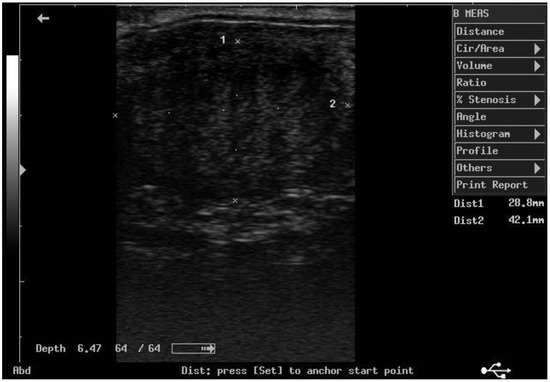

According to ultrasonographic records (Table 1), the mean T diameters did not differ significantly between PPH and NPPH at any time, whereas the mean M diameter of the PPH was larger than the NPPH only until PP Day 7 (Figure 1, Figure 2, Figure 3 and Figure 4). The Bonferroni post hoc test confirmed the ultrasonographic data obtained by ANOVA for repeated measures, when PPH and NPPH were considered across time. Moreover, when only time was assessed, the Bonferroni post hoc test highlighted similar significant changes occurring between PP Days 1–3 and 14–28 (p-value ranging between <0.05 and <0.001) and between PP Days 7 and 14–28 (p-value ranging between <0.05 and <0.01) for the M and CCJ. In relation to T, significant changes were detected among all the times of observation, with p-value ranging between <0.05 and <0.001.

Figure 3. Ultrasound image of the middle tract of the post-pregnant uterine horn, at day 14 postpartum.

The diameter of the CCJ in the PPH was not measurable until PP Day 3, then the mean diameter of the CCJ resulted larger in the PPH in comparison to NPPH only at PP Day 7. The first PP ovulation, detected by ultrasonography, occurred 11.9 ± 1.3 days after foaling. At the first PP ovulation, the follicle diameter was 45.1 ± 2.8 mm.

Altogether, the ultrasonographic findings showed that T diameters did not differ significantly between PPH and NPPH at any time, whereas the differences between the mean M and CCJ diameters of the PPH and the NPPH disappeared after PP Day 7, suggesting that uterine involution assessed by ultrasonography could be considered completed by the subsequent observation, performed on PP Day 14. These findings disagree with previous data from the same donkey breed [13], in which, in most jennies, the recovery of the normal uterine diameter was detected by PP Day 21. Even in French donkeys [11], the mean time for uterine involution was about 22 days. Those differences could be attributable to the modality and frequency of ultrasonographic monitoring (equipment, frequency, etc.) and maybe also to the different donkey breed enrolled in the study [11]. The results of the present study are more similar with data reported for the horse mare, in which by PP Days 15–16, an adequate degree of uterine involution was detectable [9,10].